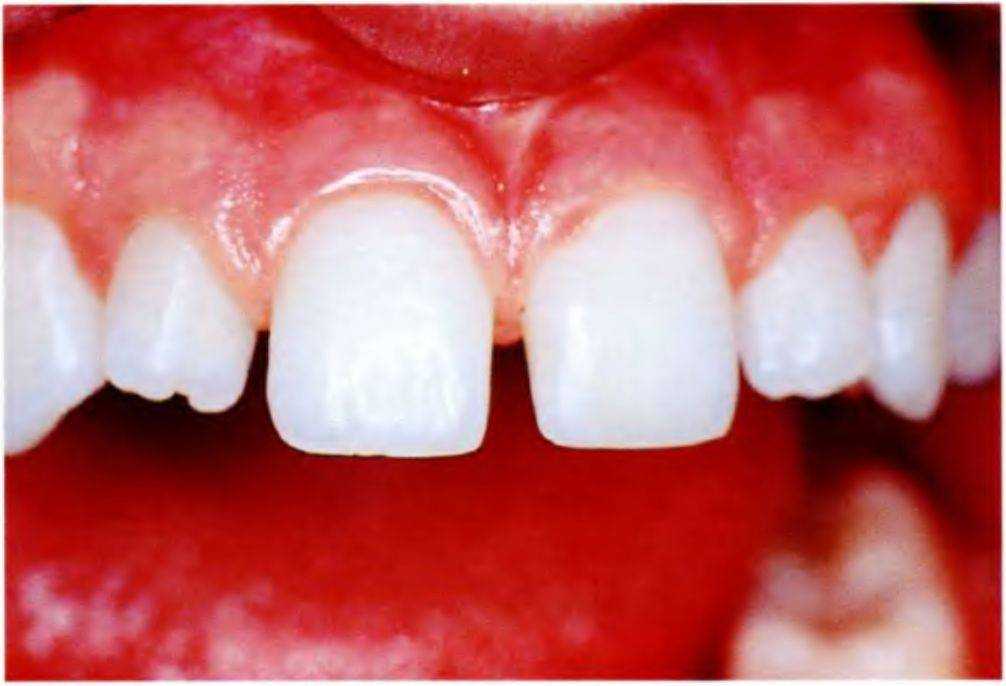

Рис. 6-12а. Исходная ситуация. Широкие пространства между передними зубами верхней челюсти

Мать 14-летней девочки обратилась в стоматологическую клинику после завершения ее ортодонтического лечения. Основное пожелание касалось устранения пространств между передними зубами верхней челюсти (рис. с 6-12с по 6-12е). Ортодонт опре-

делил, что верхние зубы слишком узкие, поэтому устранение этих пространств ортодонтическими методами будет невозможно, и направил пациентку для проведения реставрационного лечения.

Стоматологическое обследование подтвердило мнение ортодонта. Межзубные пространства в переднем отделе верхней челюсти были слишком широкими, боковые резцы повернуты вокруг своей оси. Мать девочки предпочла адгезивные реставрации для максимального сохранения тканей зубов.